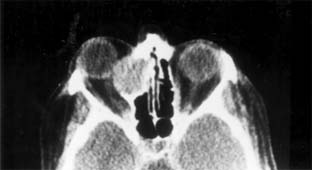

The proximity of the orbit to the paranasal sinuses may lead to invasion of the bony walls and extension of an obstructed sinus into the orbit. Plain x-ray will usually make the diagnosis, but CT or MRI may be required to differentiate sinus mucocele from dermoid cyst and to define the extent of the lesion (Figure 13-5). Otolaryngologic and neurosurgical assistance may be necessary for surgical removal.

Figure 13-5

Figure 13-5: CT scan of ethmoid sinus mucocele.